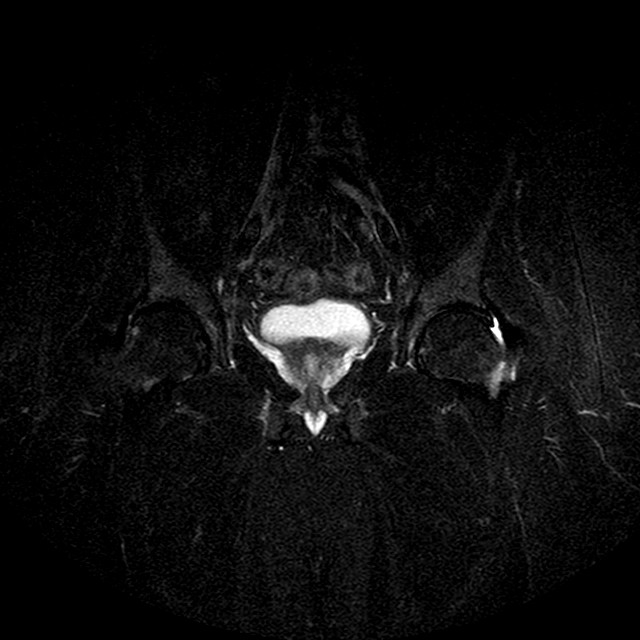

Esami: RMN BACINO

STIR

Evidenti e simmetriche alterazioni osteofitosiche in regione coxo femorale con riduzione delle rime articolari. Degenerazione completa del cercine glenoideo. Non attuali segni di versamento articolare. Non segni di edema osseo che escludono attuale algodistrofia od osteonecrosi. Lieve e simmetrica riduzione del trofismo della muscolatura glutea.